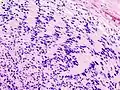

| Micrograph of a schwannoma showing both a cellular Antoni A area (top) and a loose paucicellular Antoni B area (bottom). HE stain. | |

Schwannomas are homogeneous tumors, consisting only of Schwann cells. The tumor cells always stay on the outside of the nerve, but the tumor itself may either push the nerve aside and/or up against a bony structure (thereby possibly causing damage). Schwannomas are relatively slow-growing. For reasons not yet understood, schwannomas are mostly benign and less than 1% become malignant, degenerating into a form of cancer known as neurofibrosarcoma. These masses are generally contained within a capsule, so surgical removal is often successful.[3]

Verocay bodies are seen histologically in schwannomas.

Antoni A area of schwannoma with Verocay bodies (one annotated by circle)_Antoni_B.jpg.webp)